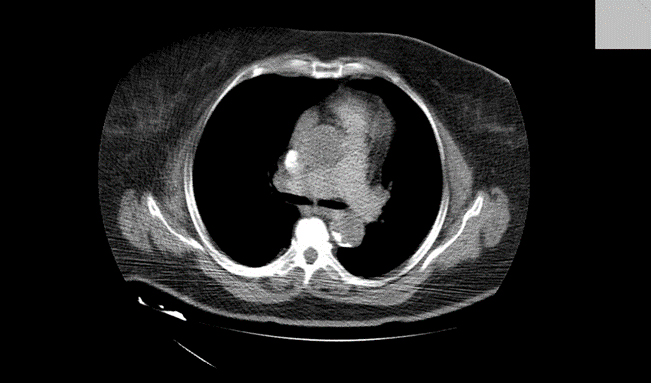

When the operation was done, the patient was awakened, extubated, and placed into the ward. After a short period of time, the patient developed breathing-dyspnea with cyanotic skin and mucous membranes. The patient was awake, on auscultation there were decreased breath sounds. Saturation – Sp02-59-83% was with oxygen mask. Immediately we gave methylprednisolone 120mg, dexamethasone 4mg, aminophylline 250mg, furosemide 20mg, and another dose of nadroparin calcium (Fraxiparine) 0.6mg s.c. After the given therapy, the condition did not improve. Due to the drop in saturation and no improvement in her overall condition and symptoms, the patient was transported to the intensive care. We intubated her, after which she was placed on mechanical ventilation and her saturation improved significantly to 99%. Propofol sedation was started. At that time, we suspected that patient might be developing pulmonary embolism. A chest X-ray was taken, where reduced transparency was noted on the left side of the lung in the middle and basal parts, as well as an increased cardiac shadow. Cardiomegaly is a very common X-ray sign in patients with pulmonary embolism ( PE) (5). After the X-ray image, a CT angiography was performed, defect in the filling of the pulmonary artery of the lower lobe in the left lung was noted, truncus pulmonalis and other pulmonary arteries were in the reference value.

Figure 1. Thromboembolism shown on CT with contrast.

We discussed whether we should include thrombolytic therapy with streptokinase drugs. Because of the fear of bleeding, we decided to continue with factor Xa inhibitors – Nadroparin calcium. Hemostasis was done and d-dimers were 9000ngr/ml. In consultation with doctor specialist – transfusiologist, Amp.Nadroparin calcium (Fraxiparine) 2×0.6ml, or 5700 I.E. were prescribed s.c. The next day, 12 hours after intubation sedation was turned off. The patient was awake, on auscultation vesicular breathing, slightly weakened on left basal part of left lung. We placed her on continuous positive airway pressure-CPAP Fi02=0.5; PEEP=0.5 Sp02-99%. Her condition was improving hour by hour and we transported her to the ward. Blood tests were done every day, on the first day post-operatively, there was reduction of blood elements and reactive leukocytosis as a result of anemia. We substituted blood through transfusion of erythrocytes, and the condition was improving. The drain was removed on the first postoperative day. The operative wound was without signs of inflammation and infection. Other inflammatory parameters such as sedimentation were normal, C-reactive protein was slightly elevated. Therefore, a swab from the wound was taken. It was negative for pathogenic aerobic and anaerobic bacteria and fungi were not detected. Physical medicine was performed during the entire hospital stay, from the second day post-operatively was in vertical position, good condition and instruction for home were given. At home, she would need to regulate her blood sugar – glycemia, to receive her chronic therapy, as well as to continue with Amp.Nadroparine calcium (Fraxiparine) 0.8ml -7600 I.E. s.c. for 14 days and Tbl.Rivaroxaban 15mg 2×1. To continue with regular blood checks for hemostasis and d-dimers and according to the results to continue therapy.